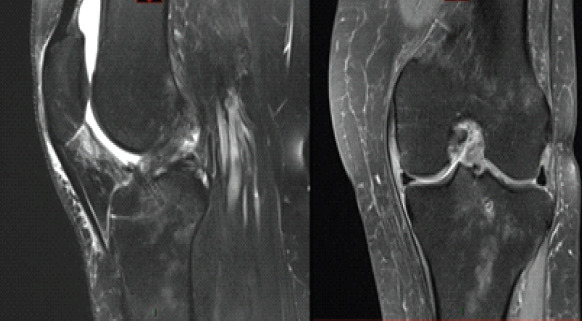

Case report: The authors present a case of a 60-year-old Caucasian female who developed a femoral-sided cyclops lesion after ACL repair. After initially achieving full range of motion (ROM) post-surgery, the patient later experienced a palpable clunk and extension loss 3-months postoperatively. While magnetic resonance imaging (MRI) was unremarkable, subsequent arthroscopy confirmed the diagnosis, leading to successful lesion excision and notchplasty.